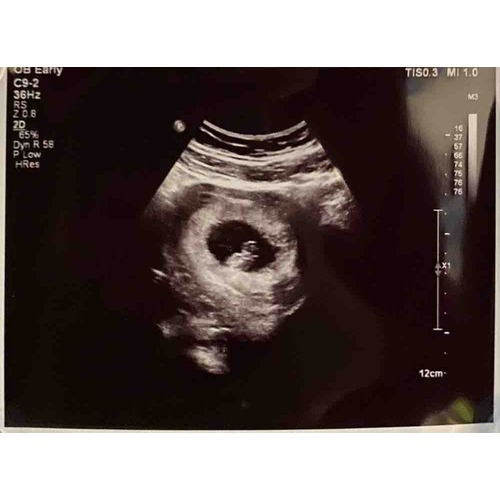

Mijn echo, dacht 7+5 te zijn maar de metingen kwamen overeen met 9+1 🥰